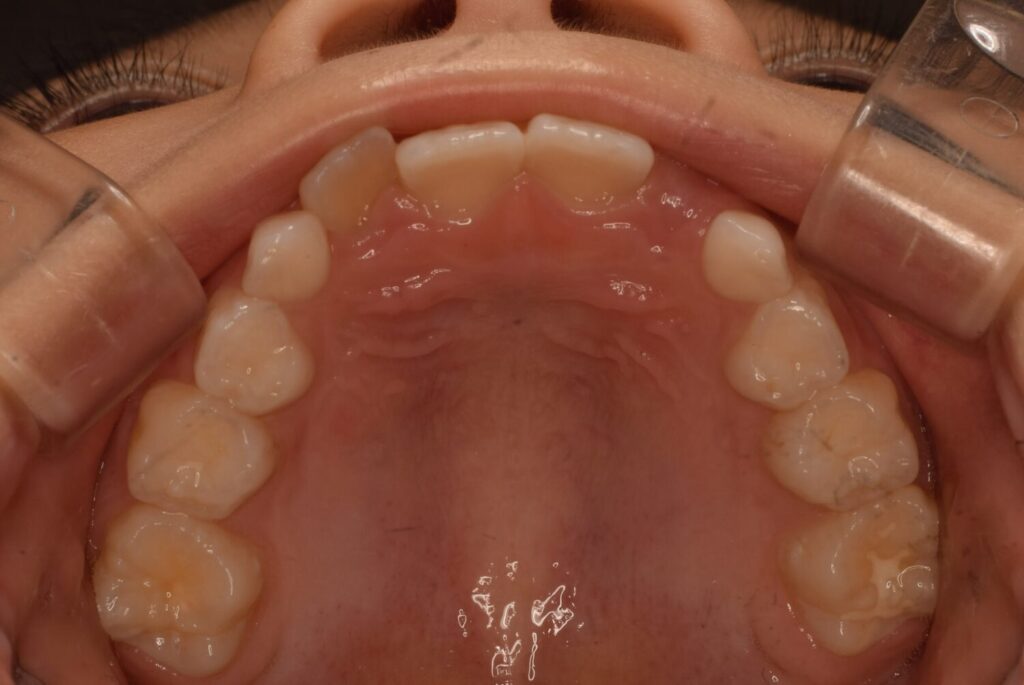

上の歯並びの変化

上の歯並びも3ヶ月後に見ると左の前から2番目の歯が綺麗に入っています。

ですが反対側の歯がまだ入りません。

でも確実に顎は大きくなってきています!

次の生え変わりは3番目の歯です。

この歯は根っこが長く、よく八重歯と呼ばれ、外側が出ているような歯になることが多いです。

実際に生えてくるとこのように大きい歯が出てきます。

幅が足りずこのままでは八重歯になってしまいそうでした。